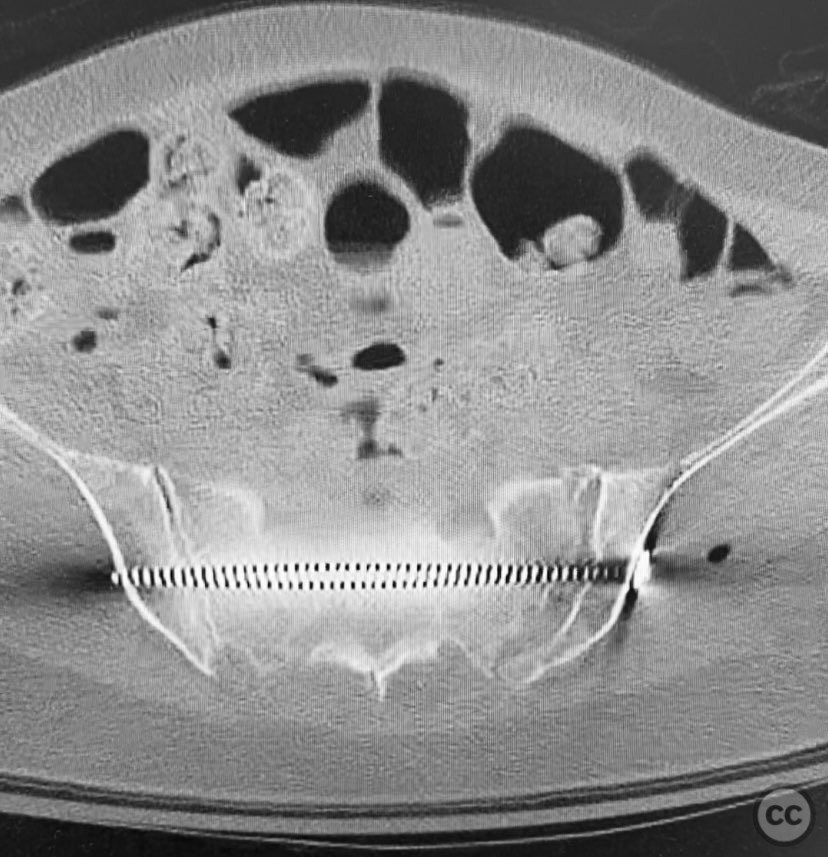

Clinical and radiological findings:  A 74-year-old female presented following a fall from standing height, unable to mobilize due to severe pelvic pain (9/10). Examination under anesthesia with fluoroscopic assessment (AP and inlet views) demonstrated instability and displacement of the pelvic ring with minimal manual compression at the iliac crests. Imaging revealed left-sided posterior iliac/sacral and pubic ramus fractures consistent with an AO/OTA 61-B2 (lateral compression type) pelvic ring injury. No neurovascular deficits were noted.

Planning remarks:  The preoperative plan involved closed reduction of the pelvic ring under fluoroscopic guidance, followed by percutaneous screw fixation of the left posterior iliac/sacral region and the ipsilateral pubic ramus. Detailed preoperative CT imaging was used to plan safe osseous corridors for screw placement, correlating with intraoperative fluoroscopic landmarks.

Anatomical surgical approach:  Percutaneous technique was employed. Small stab incisions were made over the lateral aspect of the pelvis. Under continuous fluoroscopic guidance, guidewires were advanced through the ilium into the sacrum (iliosacral region) and through the superior pubic ramus. Cannulated screws were then inserted over the guidewires, ensuring extra-articular and intraosseous positioning within the safe bone corridors as determined by preoperative CT analysis.

Intraoperatively, manual manipulation of the pelvis was performed to achieve improved reduction prior to fixation. The stability achieved by percutaneous screw fixation provided immediate symptomatic relief, allowing for early mobilization. The procedure emphasized meticulous attention to fluoroscopic imaging and preoperative CT planning to avoid neurovascular compromise and optimize screw trajectory within osteoporotic bone.

Orthopaedic implants used:   Cannulated iliosacral screw, cannulated pubic ramus screw